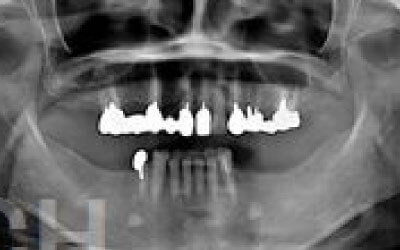

ブリッジとインプラントでは、周りの歯の寿命に大きな違いがあります。ブリッジは支えとなる歯を健康でもかなり削らなければならず、さらに噛む力が約1.5倍かかるため、その歯の寿命が短くなってしまいます。実際のデータでは、ブリッジの支えとなった歯の68%が10年以内に抜歯に至っています。

ブリッジ治療の場合も、失った歯にかかっていた力を前後の歯が支えるため、結果として残っている歯には、通常の1.5〜2倍ほどの負荷がかかってしまいます。

入れ歯の場合、バネをかけている歯や残っている歯に大きな負担がかかります。多くの方が無意識のうちに残った歯で噛むため、その歯にかかる回数や力が過剰になり、結果的に歯が折れるなど寿命を縮めてしまうことがあります。一方、インプラントは人工の歯根を骨に直接埋め込むため、力を骨が受け止めることができ、残っている歯への負担は格段に少なくなります。

ブリッジなどの治療では、前後の歯を大きく削らなければならず、場合によっては虫歯でなくても神経を抜くことがあります。神経を抜いて被せ物をすると、その歯は一気に寿命の終わりに近づいてしまうのです。

一方でインプラント治療なら、前後の歯を削ったり神経を取ったりする必要がなく、健康な歯をできるだけ守ることができます。歯の寿命を延ばすためにも、なるべく歯を削らないことは非常に重要です。

最も大きな違いは、前後の歯の寿命に影響を与えることです。

ブリッジでは、抜けた歯の前後の歯を大きな虫歯と同じくらいまで削らなければならず、

また、抜けた歯の代わりに前後の歯がその力を支えるため、常に1.5倍の負荷がかかります。

1)ブリッジ

2)歯を大きく削る+支えの歯に1.5倍の力がかかる

3)前後の歯の寿命が著しく減る

ブリッジの支えの歯は、データでは10年以内に68%が抜歯になります。